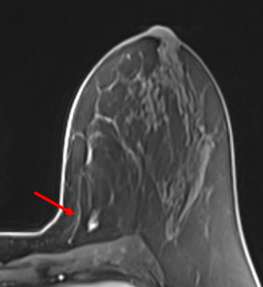

When LCIS is seen on MRI, the most common finding is non-mass enhancement. Most of the non-mass enhancement show persistent enhancement on delayed phase4.